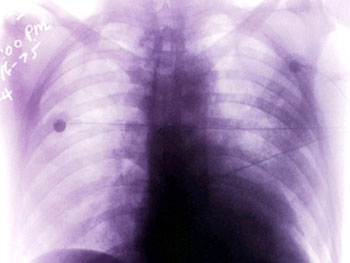

Thể phổi là thể đáng sợ nhất vì bệnh tiến triển nhanh và có nguy cơ lây lan cao. Người bệnh có biểu hiện triệu chứng như: sốt cao, rét run, đau đầu, hoa mắt, chóng mặt, bứt rứt. Khoảng 24 giờ sau đó bệnh nhân có những triệu chứng tổn thương tại phổi như: đau tức ngực, khó thở, thở nhanh, ho có chất đờm nhầy và loãng sau đặc dần; chất đờm có máu hoặc có nước bọt. Bệnh dịch hạch thể phổi có khả năng lây lan rất mạnh do vi khuẩn dịch hạch dễ dàng phát tán từ người bệnh sang người lành qua nước bọt, đờm dãi khi ho hoặc hắt hơi. Nếu khi bị mắc bệnh mà không được phát hiện, chẩn đoán và điều trị sớm thì hầu hết tất cả các trường hợp bệnh dịch hạch thể phổi đều dẫn đến tử vong.

Bệnh dịch hạch thể hạch và thể phổi (ảnh minh họa) |